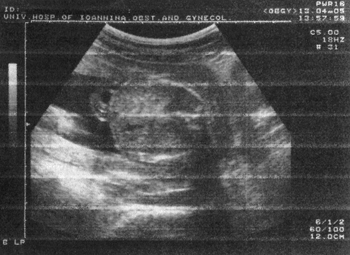

Εικόνα 1. CRL. Κεφαλοουραίο μήκος εμβρύου. Εκτίμηση ηλικίας κύησης 1ου τρίμηνου. Εικόνα 2. BPD. Αμφιβρεγματική διάμετρος κεφαλής εμβρύου. Εκτίμηση ηλικίας κύησης 2ου τριμήνου.

BPD (εικόνα 2)

Προκύπτουν διαφορές της τάξεως των 0.5cm και αντίστοιχα 7-21 ημερών κατά τη διάρκεια του 2ου και 3ου τριμήνου, οι οποίες οφείλονται στον τρόπο μέτρησης της ΒPD, π.χ. κάποιοι μετρούν τη BPD έξω - έξω, άλλοι μέσα - έξω. Οι διαφορές αυτές βρίσκονται μέσα στο όριο ασφαλείας των 3 εβδομάδων.

Το καλύτερο, όμως, είναι να εντάξουμε κάθε κύηση στα δικά της δεδομένα και να έχουμε δύο μετρήσεις. Η αναφορά και η σύγκριση με προηγούμενη μέτρηση και ο σχεδιασμός της ατομικής καμπύλης ανάπτυξης κάθε εμβρύου περιορίζει την πιθανότητα λάθους μεγαλύτερου από το αποδεκτό για το συγκεκριμένο τρίμηνο.(12,16)

Η BPD είναι η πιο ακριβής μέθοδος προσδιορισμού στο 2ο τρίμηνο της κυήσεως.

Αν υπάρχει διάσταση μεταξύ ΤΕΡ και υπερηχογραφικών μετρήσεων, δεχόμαστε τη BPD στο 2ο τρίμηνο ως την πιο αξιόπιστη παράμετρο για τον προσδιορισμό της ηλικίας κύησης, ή την HC σε περιπτώσεις δολιχοκεφαλίας ή σε τιμές κεφαλικού δείκτη εκτός των οριζόμενων ως φυσιολογικών.